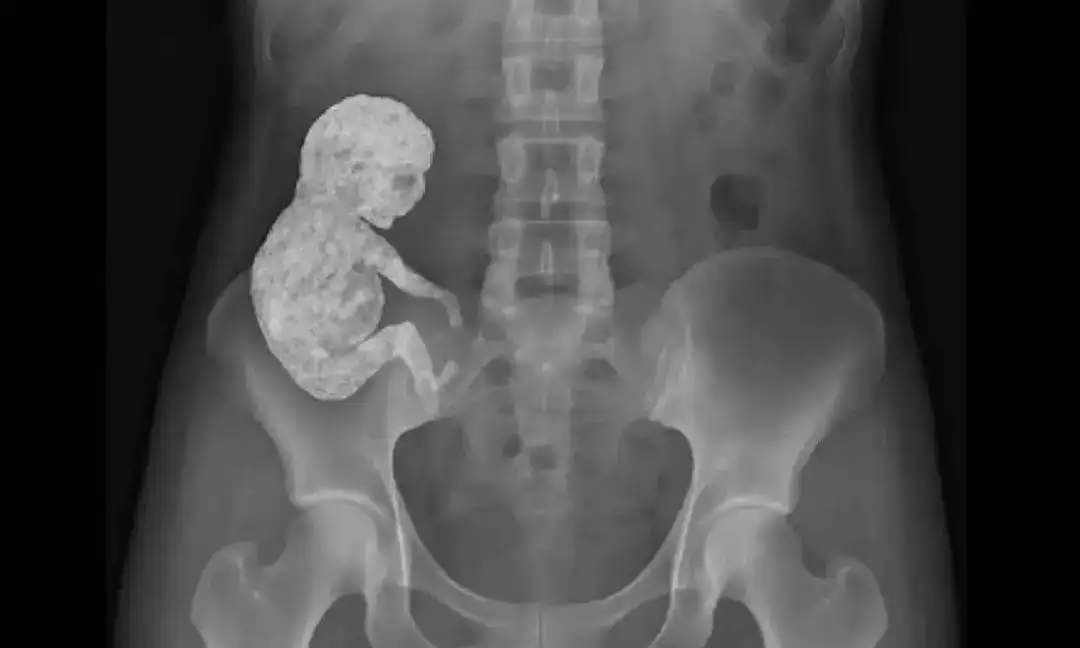

40 ఏళ్ల పాటు గర్భంలో శిశువు.. 82 ఏళ్ల వయసులో బయటపడ్డ షాకింగ్ నిజం | Stone Baby Case

ఏకంగా 40 సంవత్సరాల పాటు గర్భంలో శిశువును మోసిన మహిళ కథ ఇప్పుడు ప్రపంచాన్ని ఆశ్చర్యపరుస్తోంది. 82 ఏళ్ల వయసులో ఆస్పత్రికి వెళ్లిన ఆమెకు బయటపడిన షాకింగ్ నిజం ఇదే.